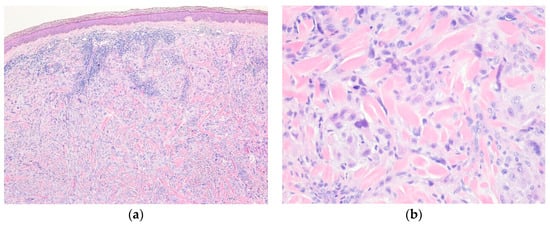

4.1. Cutaneous Smooth Muscle Tumors

4.2. Glomus Tumor